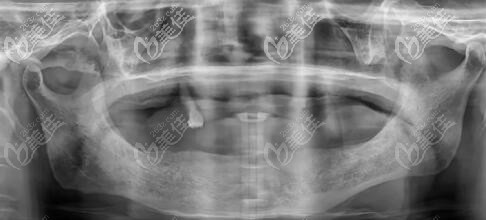

高老师做上半口6颗、下半口4颗种植牙后的CT图片▲

他做的全口即刻负重种植牙只用了10颗植体(上半口6颗,下半口4颗)